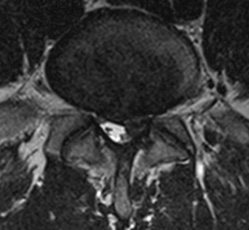

Axial T2 weighted image of the lumbar spine. The same L4-5 disc protrusion is potentially compromising the descending left L5 nerve root.